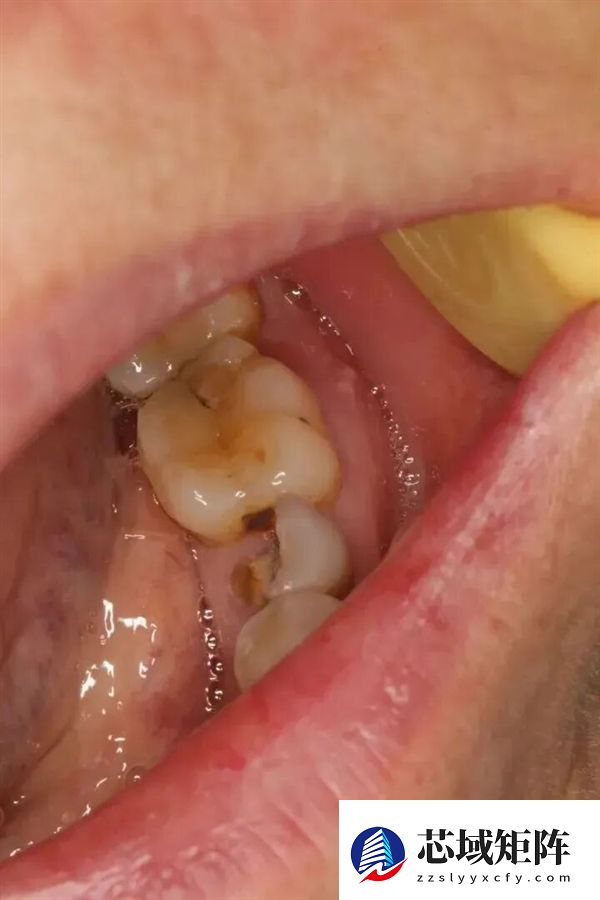

1、残根牙冠

比如很多人嘴里有残根残冠(烂到牙根无法治疗保留的牙齿、经久不治长期发炎肿包的病牙),这些牙齿周围本就藏着大量细菌,虽然可能只是偶尔疼一下,也没有特别的疼痛不适;但因为进行了化疗等肿瘤药物治疗后,口腔黏膜变得脆弱,细菌容易突破黏膜屏障,就可能会引发口腔溃疡、急性牙髓炎、根尖周炎、牙龈炎、牙周炎、智齿冠周炎等,甚至扩散成全身引发严重的感染(如败血症)。

口腔内残损的牙齿。图源:作者提供